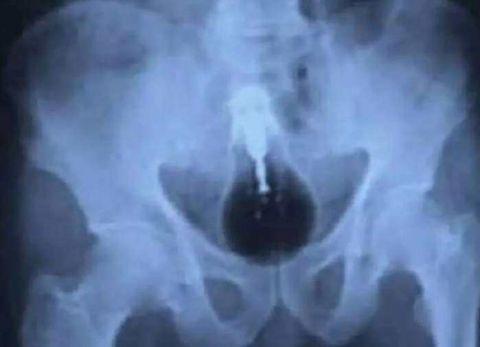

一支圆珠笔,话说这么细会舒服么?